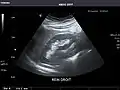

Kidneys: Right and left kidneys measure 11.5 cm and 12 cm in length respectively. No hydronephrosis. Small left lower pole kidney cyst.

Right kidney